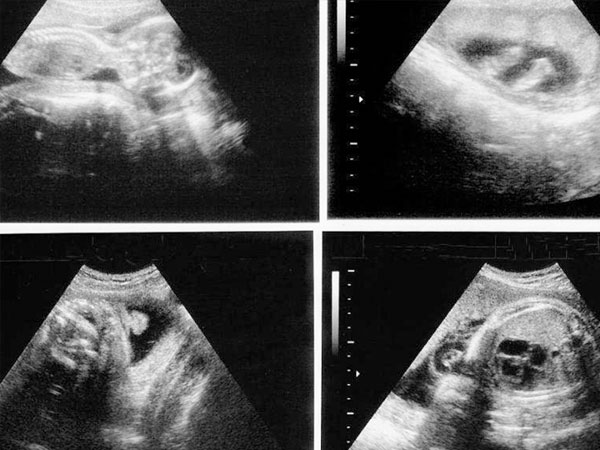

女性怀孕之后去医院做产前检查的时候会进行多次的b超检查,而目前有不少人说通过b超检查单子就可以看出胎儿的性别,甚至还有人总结了一些明显是女孩的数据,具体如下:

图像信息:如果b超单上胎儿的双腿之间有三条线,那说明是个女孩;

孕囊形状:通过观察孕囊形状就能看出胎儿的性别,一般形状是椭圆或圆形的是女孩;

孕囊大小:如果孕囊长和宽一样或者相差不是很大说明是女孩;

上方字母:有些医院的b超单上会有x字母或y字母,一般这也暗示了胎儿的性别,出现x字母时,就说明是个女孩。

以上就是通过b超单来看是否是女孩的方法,但其实这些数据和说法都没有任何的科学依据,只是民间总结的一些说法而已,不具有可信度,大家不要太过当真,简单的了解一下就好了。